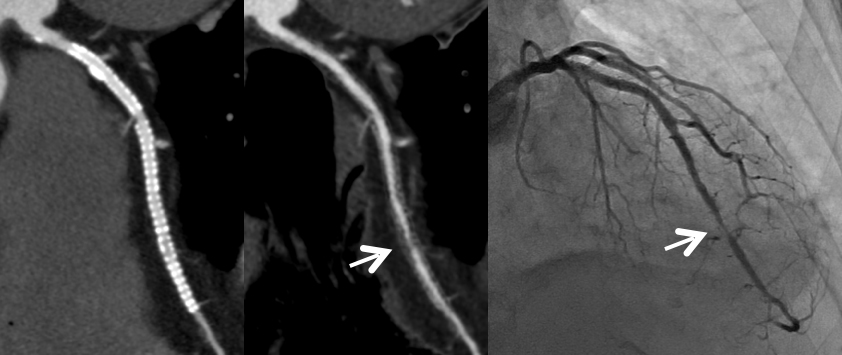

通常の画像(左)ではSTENT内の評価は困難ですが、サブトラクション画像(中央)によって末梢側に高度狭窄を疑われます(矢印)。カテーテル造影(右)でも同様の位置に高度狭窄病変を認めます(矢印)。

Yamaguchi T. Ichikawa K, Takahashi D. et.al. A New Contrast Enhancement Protocol for Subtraction Coronary Computed Tomography Requiring a Short Breath-Holding Time. Academic Radiology Published online: October 17, 2016